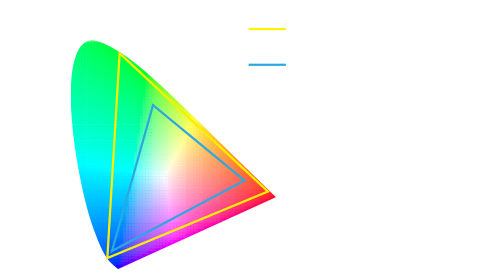

Wide Color Gamut

Restore the organs and tissues in real color, perfect identification of blood vessels, lymph nodes and nerves.